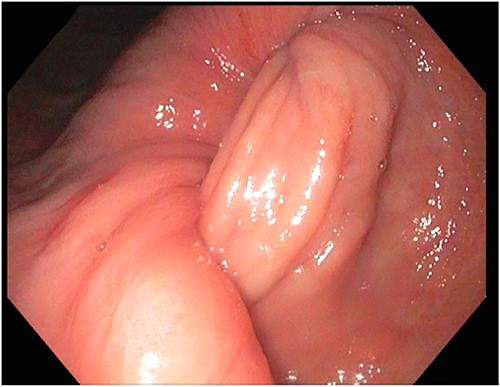

After a few days, the patient was found to have a large volume of melenic stool. A CT angiogram of the chest, abdomen and pelvis was done, revealing a mass in the antrum and pylorus of the stomach with a portion of the stomach pulled into it, consistent with gastroduodenal intussusception without any active extravasation. Repeat EGD showed a large, fungating, pedunculated mass with no bleeding and no stigmata of recent bleeding in the gastric body (Figs. 3 and4) and confirmed gastroduodenal intussusception. The intussusception spontaneously reduced while attempting to push passed the mass. The mass was too large to resect endoscopically. Given these new findings, the family agreed to surgical intervention. An exploratory laparotomy was made, and the patient underwent partial gastrectomy, distal antrectomy and Billroth II procedure. The resected large gastric body mass within the mid gastric body and two nodes were sent for frozen section and immunohistochemical analysis. The pathology report confirmed the mass as a GIST, spindle cell type with no significant nuclear atypia or mitosis, arising from muscularis propria, without mucosal invasion and R0 margins. The neoplastic cells stained positive for CD117 (KIT), CD34 and Desmin (focally). The tumor was T3N0M0 with a low mitotic rate, histologic grade G1 and was deemed low risk (3.6%). The patient was discharged to a subacute rehab with an uneventful recovery.